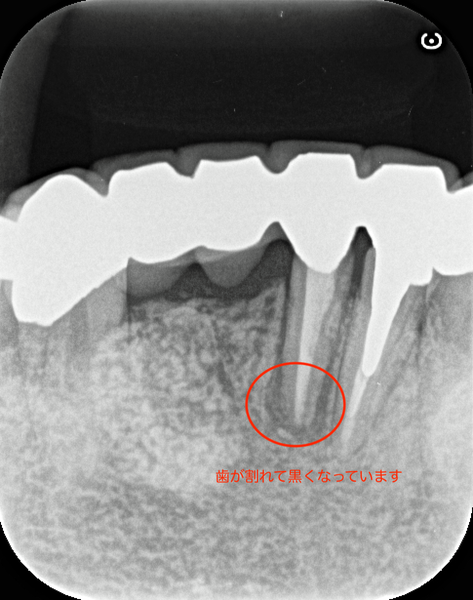

これは私自身の歯です。

私は最初に大学病院で治療を受けましたが、のちに細菌感染により根管治療をすることとなりました。原因は今にして思えば、ラバーダムなしの治療にあったのではないかと感じています。その後、別の歯科医院で口腔外科の手術を受けましたが結局、抜歯となったり、別の歯が破折を起こしたりと歯のトラブルが続きました。